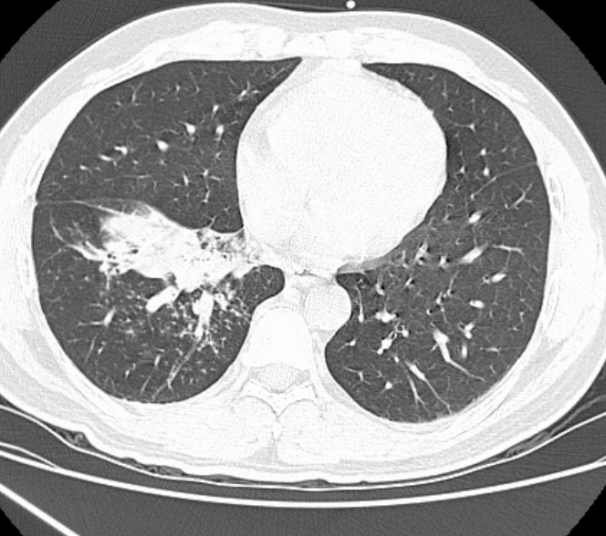

术前胸部CT

42岁的市民陈先生在食用米粉时不慎呛咳,起初并未在意,可随后反复呛咳、持续高热轮番来袭,常规对症治疗始终不见起色,病情日渐加重。焦急之下,陈先生来到我院呼吸与危重症医学科就诊。科室团队高度重视、细致研判,胸部CT提示右下肺炎症,结合明确的呛咳病史,团队快速精准判断:气道内极有可能藏着“作祟”的异物,这正是久治不愈的根源!从接诊评估、影像读片,到方案制定、术前准备,科室团队分工明确、衔接顺畅,为快速救治筑牢基础。